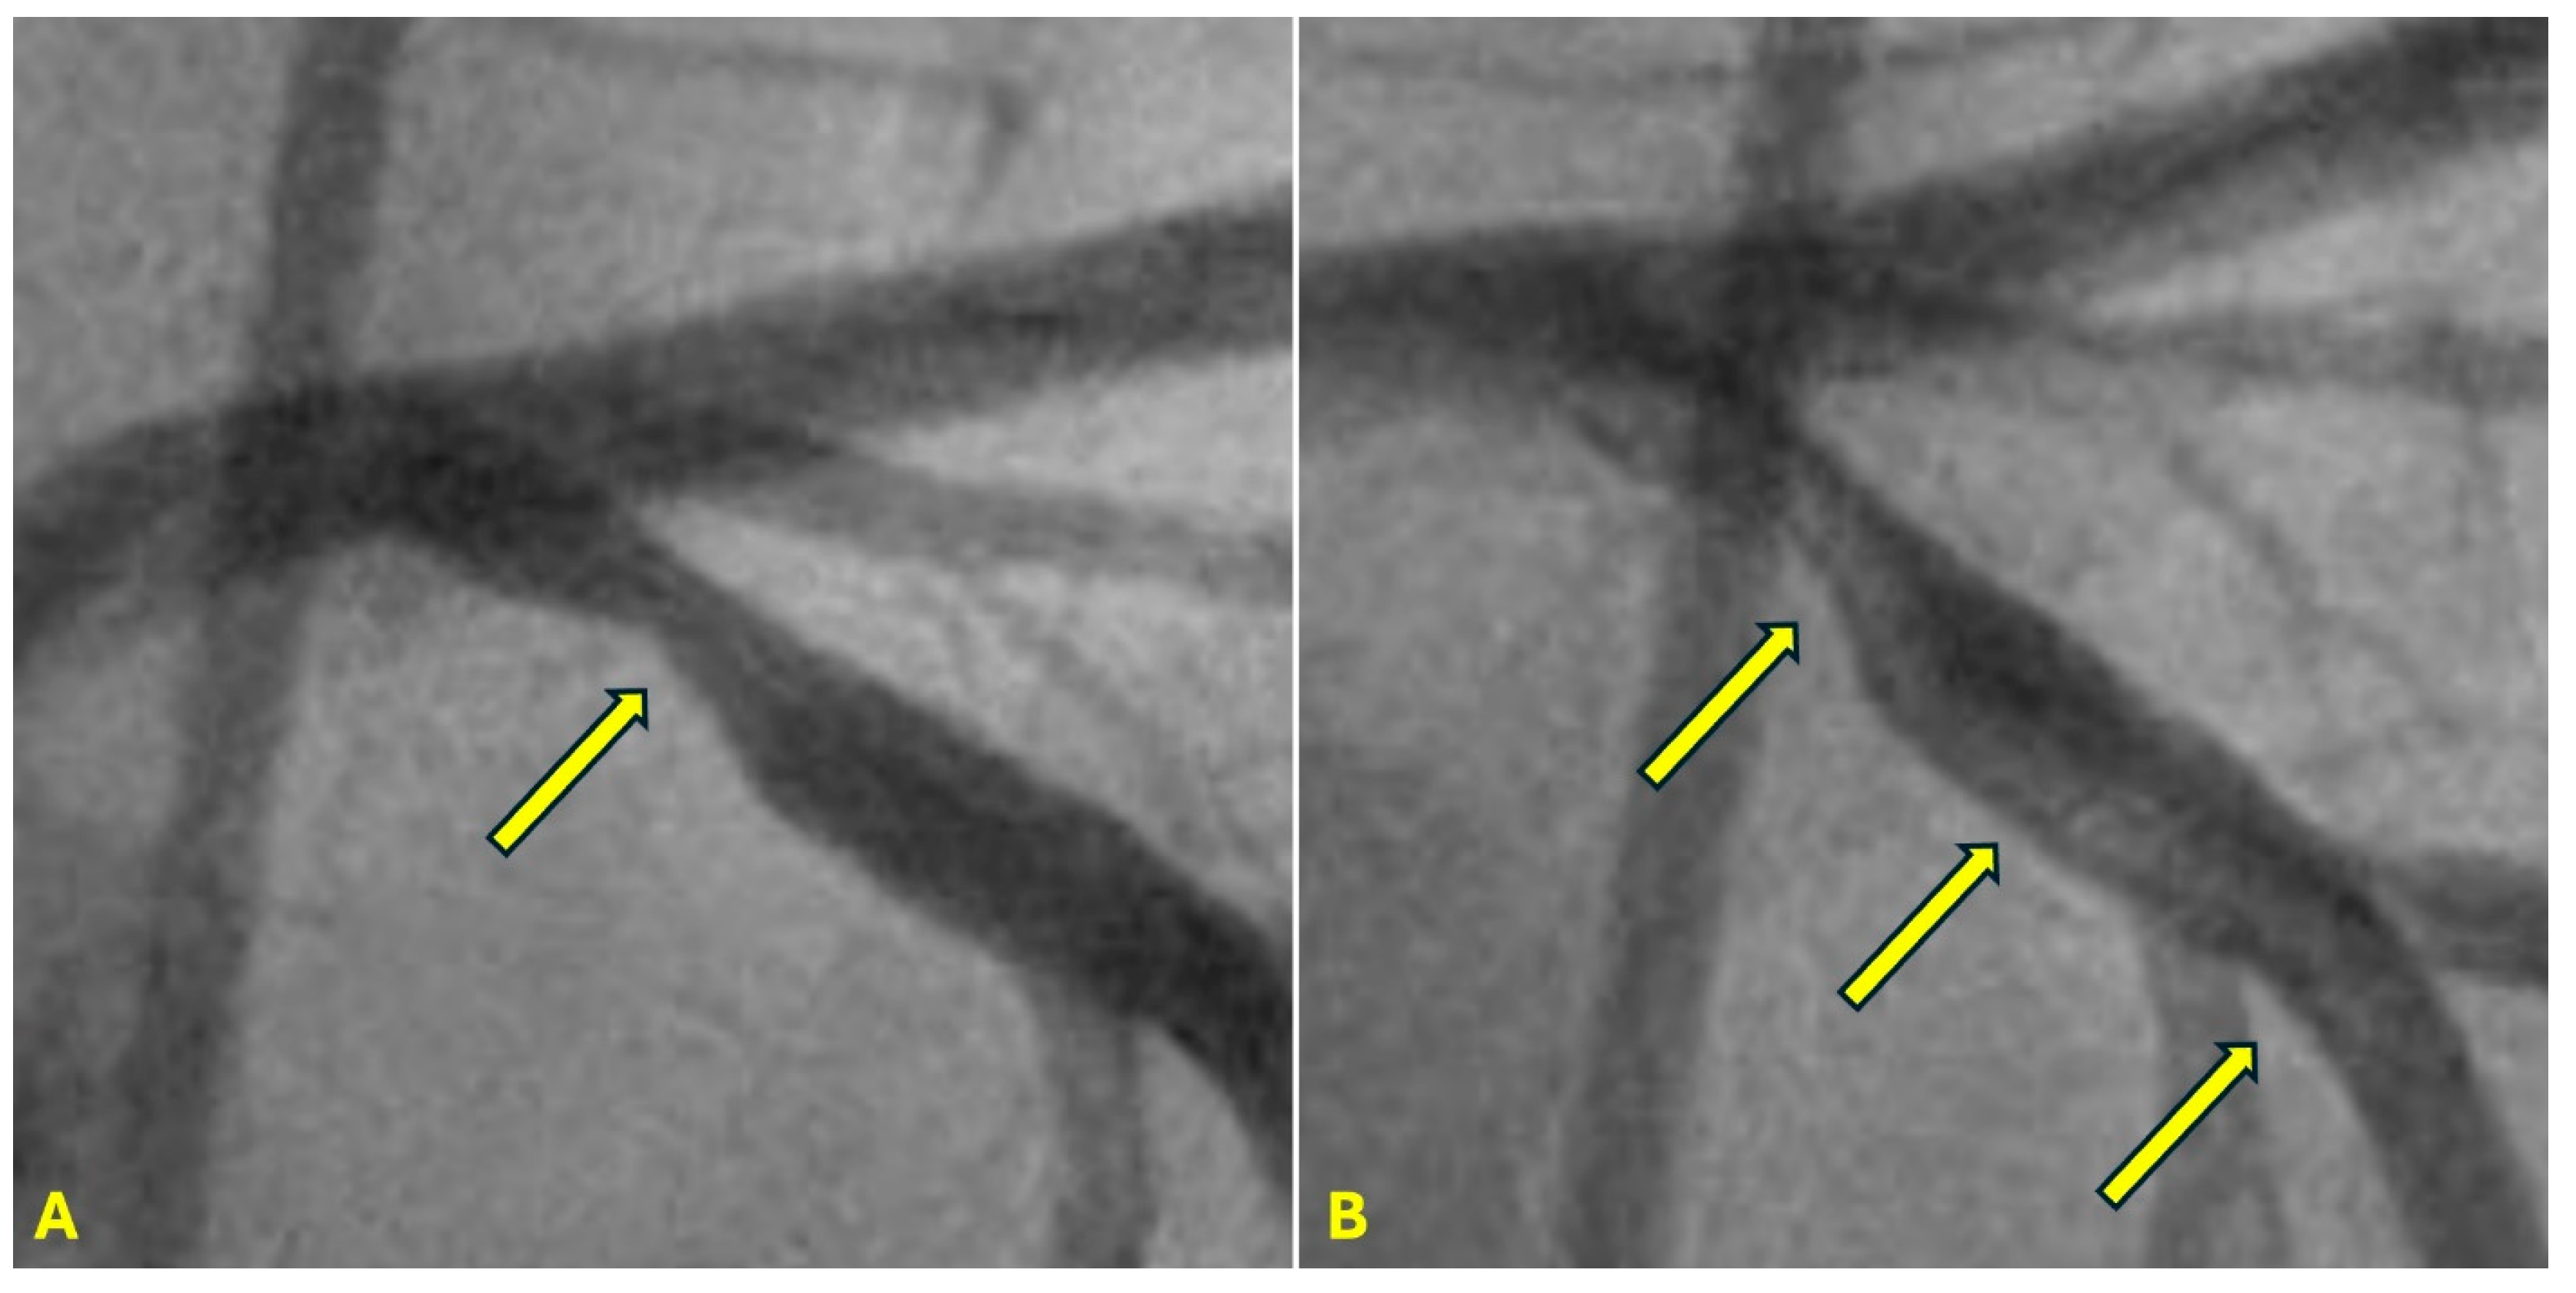

Additionally, this process elucidates the mechanism driving plaque cover rupture, which often arises at the junction between the plaque and adjacent normal tissue due to the impact of pressure waves on the mechanically unequal interface. As arterial stiffening progresses with calcification, it impedes the retrograde propagation of pressure waves [28]. This underscores the beneficial role of stenting in mitigating retrograde pressure wave effects on the new stent-scaffolded arterial wall. (Figure 11A–H).

CLINICAL APPLICATIONS Beneficial Effect of Stenting. When a patient receives a stent, the technical goal is to deploy a stent with optimal expansion of the lumen and well apposition of the struts to the arterial wall. The fluid mechanics and acoustics goals are to develop a laminar antegrade flow during diastole, with no reversed flow, and with minimal boundary layers due to resistance from the metallic stent scaffold (Figure 11A–H). This restoration of laminar flow reduces the risk of both early thrombosis and late restenosis. The reason why there is no pressure wave reflection from a water hammer event is because the blood pressure is very well controlled during PCI, and the stented segment of the artery breaks the undulating movement of the arterial wall from pressure wave [42].

From a fluid mechanics perspective, the beneficial mechanism of stenting should not be merely described as opening a flow channel to the distal segment of the coronary artery. Instead, it is more accurately characterized as restoring laminar flow within the coronary artery and mitigating retrograde pressure waves associated with water hammer phenomena. This refined understanding extends the concept of beneficial mechanisms to include plain balloon angioplasty (POBA) and drug-coated balloon angioplasty (DCB) [43].